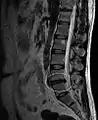

МРТ великих гриж (праворуч) диска L4-L5.

МРТ поперекового міжхребцевого диска між четвертим і п'ятим хребцями.

Досить велика кила L4-L5.

Приклад міжхребцевого диска L5-S1 у поперековому відділі хребта.